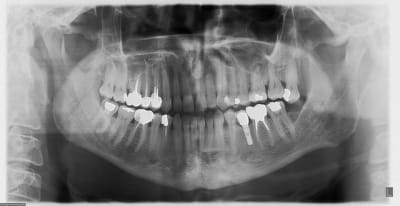

Voici 2 panos avec 2 systèmes différents. Dans un cas c'est une connectique hexagone externe en place depuis 1991 le controle date de 2012.

La 2ème est un controle à 3 ans. Seulement voilà les cas d'os au dessus du col ne sont que trop rarissimes et dans des cas tout à fait exceptionnels. Je pense qu'ils dépendent plus de la qualité de gestion que du matos.

Perso: obtenir de l'os au niveau de la connectique est due plus à la vascularisation osseuse qu'à la connectique à proprement parlé, d'où l'importance de la cicatrisation.